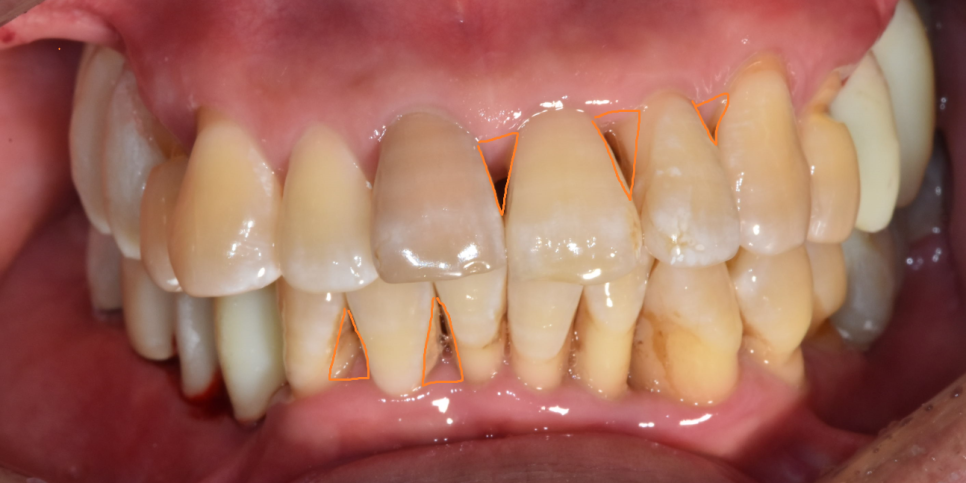

- 잇몸 퇴축

잇몸이 치아 뿌리 부분까지 내려가면서

치아가 길어보이거나 치아 뿌리가 드러나게 됩니다.

나이가 들면서 치아가 길어보이거나

치아 사이 사이 틈이 벌어졌다면 잇몸이 내려갔나?

의심해보셔야해요!!